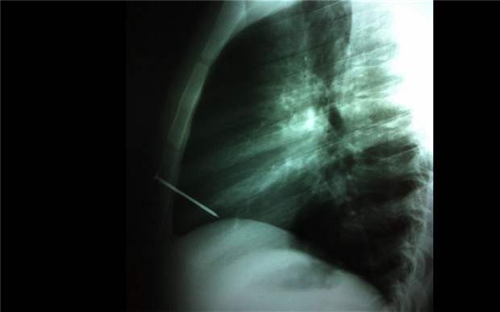

អន្តរជាតិ ៖ បើតាមការអោយដឹងពីទំព័រសារព័ត៌មានបរទេស Happening ដែលទើបតែបានចេញផ្សាយកាលពីវេលាល្ងាចម្សិលមិញនេះ បានបញ្ជាក់អោយដឹងថា ជាងឈើវ័យក្មេងជនជាតិអាហ្សង់ទីនម្នាក់ ត្រូវបានរកអោយឃើញថា ពិតជាមានសំណាងហួសពីការស្មាន ស្របពេលដែលនៅរស់រានមានជីវិត បន្ទាប់ពីដែកគោល ប្រវែង ៣ អ៊ីង ត្រូវបានបាញ់ដោយអចេតនាចំបេះដូងរបស់គេ។

គួរបញ្ជាក់ផងដែរថា ជាងឈើវ័យក្មេង វ័យ ១៩ ឆ្នាំរូបនោះ មិនទាន់ត្រូវបានបញ្ជាក់អត្តសញ្ញាណនៅឡើយទេ។ហើយបើនិយាយពីការបាញ់ដោយអចេតនាចំបេះដូងរបស់ជាងឈើរូបនេះនោះ ត្រូវបានធ្វើឡើងដោយ មិត្តភក្តិម្នាក់ផ្សេងទៀត ធ្វើការងាររួមគ្នា ដោយមានការធ្វេសប្រហែស ខណៈពេលដែលកំពុងកាន់កាំភ្លើងបាញ់ដែកគោល។

លើសពីនេះទៅទៀត ប្រភពដដែលបានបន្ថែមថា ឧបទ្ទេវហេតុចៃដន្យមួយនេះ បានកើតឡើងនៅឯរោងចក្រឈើមួយកន្លែង ដែលពួកគេកំពុងតែបំរើការងារ នៅឯតំបន់ Cañuelas ។ ភ្លាមៗនោះ ក៏មានការអន្តរគមន៍ ដោយបានបញ្ជូនគាត់ទៅកាន់មន្ទីរពេទ្យ ដើម្បីធ្វើការសង្គ្រោះបន្ទាន់ ។ ជាលទ្ធផល បន្ទាប់ពីមានការវះកាត់ គាត់មិនបានស្លាប់បាត់បង់ជីវិតនោះទេ ខណៈពេលដែលការវះកាត់ទទួលបានជោគជ័យ៕